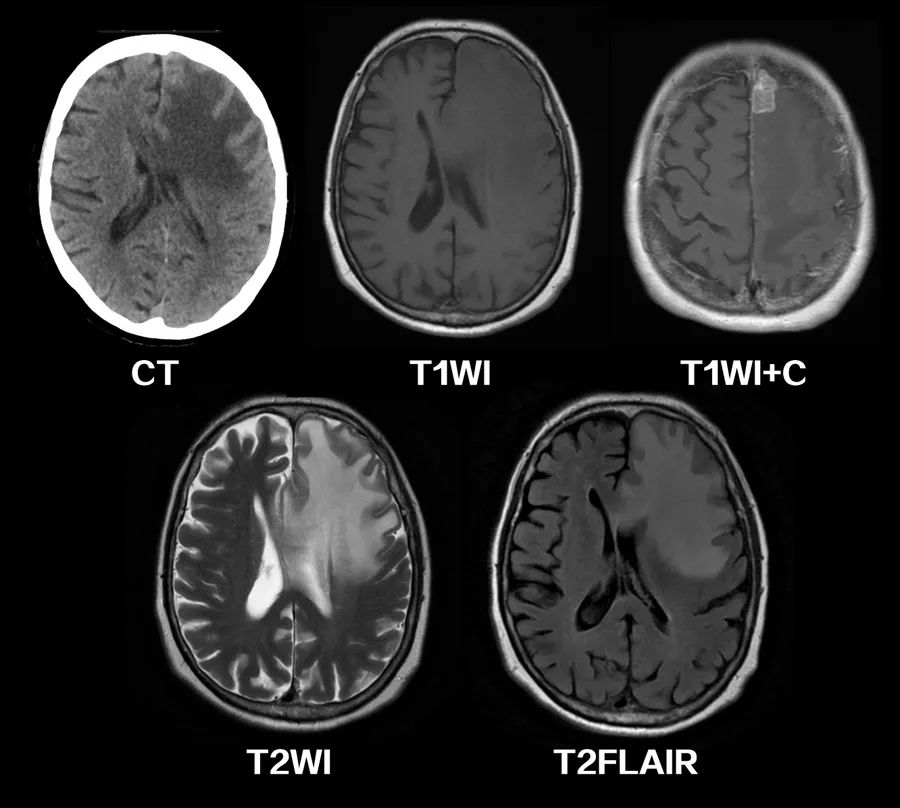

引起血管源性脑水肿的典型疾病包括脑肿瘤、脑脓肿、脑炎等,一些成熟的脑挫伤和脑出血病灶周围也可以出现血管源性脑水肿。相比之下,血管源性脑水肿在白质分布较灰质更为明显,灰白质界限仍然保持,这与离子性脑水肿的灰白质界限模糊有所不同;病变常呈手指状延伸分布模式。CT上可看到脑白质的密度减低,MRI上T1WI呈低信号,T2WI呈高信号,DWI上并不显示明显的弥散受限。

图3 40岁女性,脑脓肿,T2FLAIR像上可见病灶周围片状高信号区域,并呈手指状向周围延伸。

富含蛋白质的液体渗入脑组织可能会引起严重肿胀,造成继发性影响,CT和MRI上可检测到占位效应,出现中线结构的移位和内侧颞叶的突出等。此外,蛋白质和血液的渗漏可影响CT密度和MRI的信号,需要小心识别。

图4 乳腺癌脑转移,CT、MRI上可见广泛的血管源性脑水肿区域,侧脑室受压,中线移位。引起血管源性脑水肿的占位性病变位于左额上回。